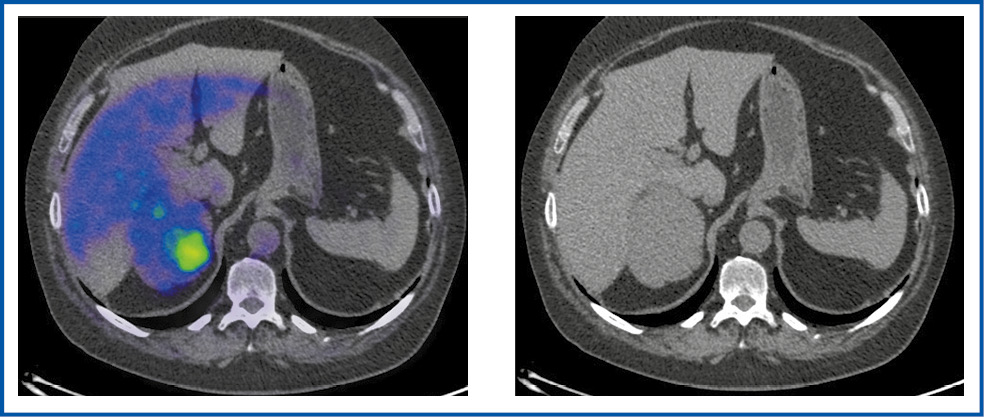

Неоднородную структуру опухоли наблюдали у 5 пациентов, кистозно-солидную – у 3, солидный характер образования – у 1 (рис. 1–4).

Рис. 1. Больная П., 40 лет. В аксиальной проекции ПЭТ/КТ- и КТ-исследовании в левом надпочечнике имеется объемное образование неоднородной кистозно-солидной структуры размером 87×75 мм, с гиперфиксацией РФП, SUVmax – 9,49.

Fig. 1. Patient P., 40 years old. Axial view of PET/CT and CT imaging: in the left adrenal gland, there is a mass lesion with a heterogeneous cystic and solid structure, 87×75 mm, with radiopharmaceutical hyper uptake; SUVmax is 9.49.